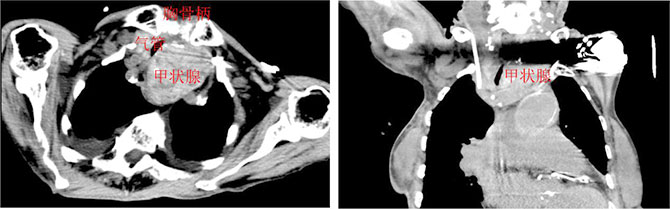

此前,因巨大胸骨后甲状腺肿压迫气管导致气道狭窄,患者出现呼吸困难等危急症状。患者曾就诊于当地医院,但由于合并慢性心衰、高血压等疾病,使得围手术期风险极高,因此被建议转至上级医院寻求更专业的治疗。

10月31日,在麻醉科于东男主任的密切配合下,在吴泽宇主任的指导下,黄毅捷主任带领手术团队为患者在全麻下行胸骨后甲状腺肿切除术。术中探查发现,甲状腺肿累及胸骨后方,至主动脉弓层面,手术难度大。在外科医生的精湛技术和团队的保驾护航下,仅1小时,便完整切除了一个9.5x5.5x5cm的巨大胸骨后甲状腺肿,术中出血极少,喉返神经和甲状旁腺均得到了完好保留。